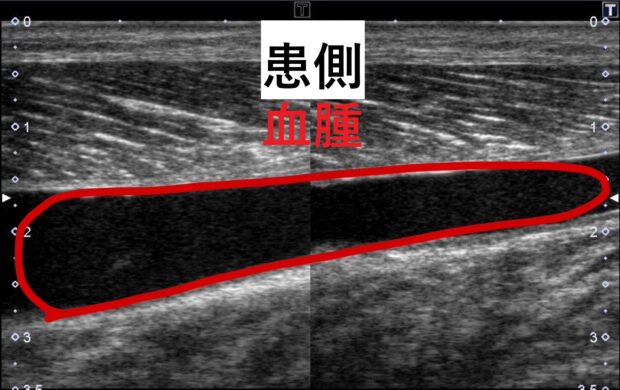

下記のエコー画像が打撲をした時の血腫(黒い部分)です。

血腫を放置すると骨化性筋炎に移行する可能性が高くなります!!